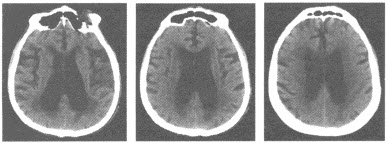

患者,男性,28岁,咳嗽咳痰1年余,CT检查如图所示。

A:左肺下叶后底端紧贴膈面呈团块状阴影

B:边界一般较清晰,其长轴指向内后方,则指示与胸主动脉有联系

C:支气管造影可见同叶的正常支气管围绕病变的移位现象

D:主动脉造影有助于确诊该疾病

E:CT增强扫描呈不均质强化,合并感染时可见气液平

F:MR多轴位扫描可现病灶内血管结构及静脉引流情况